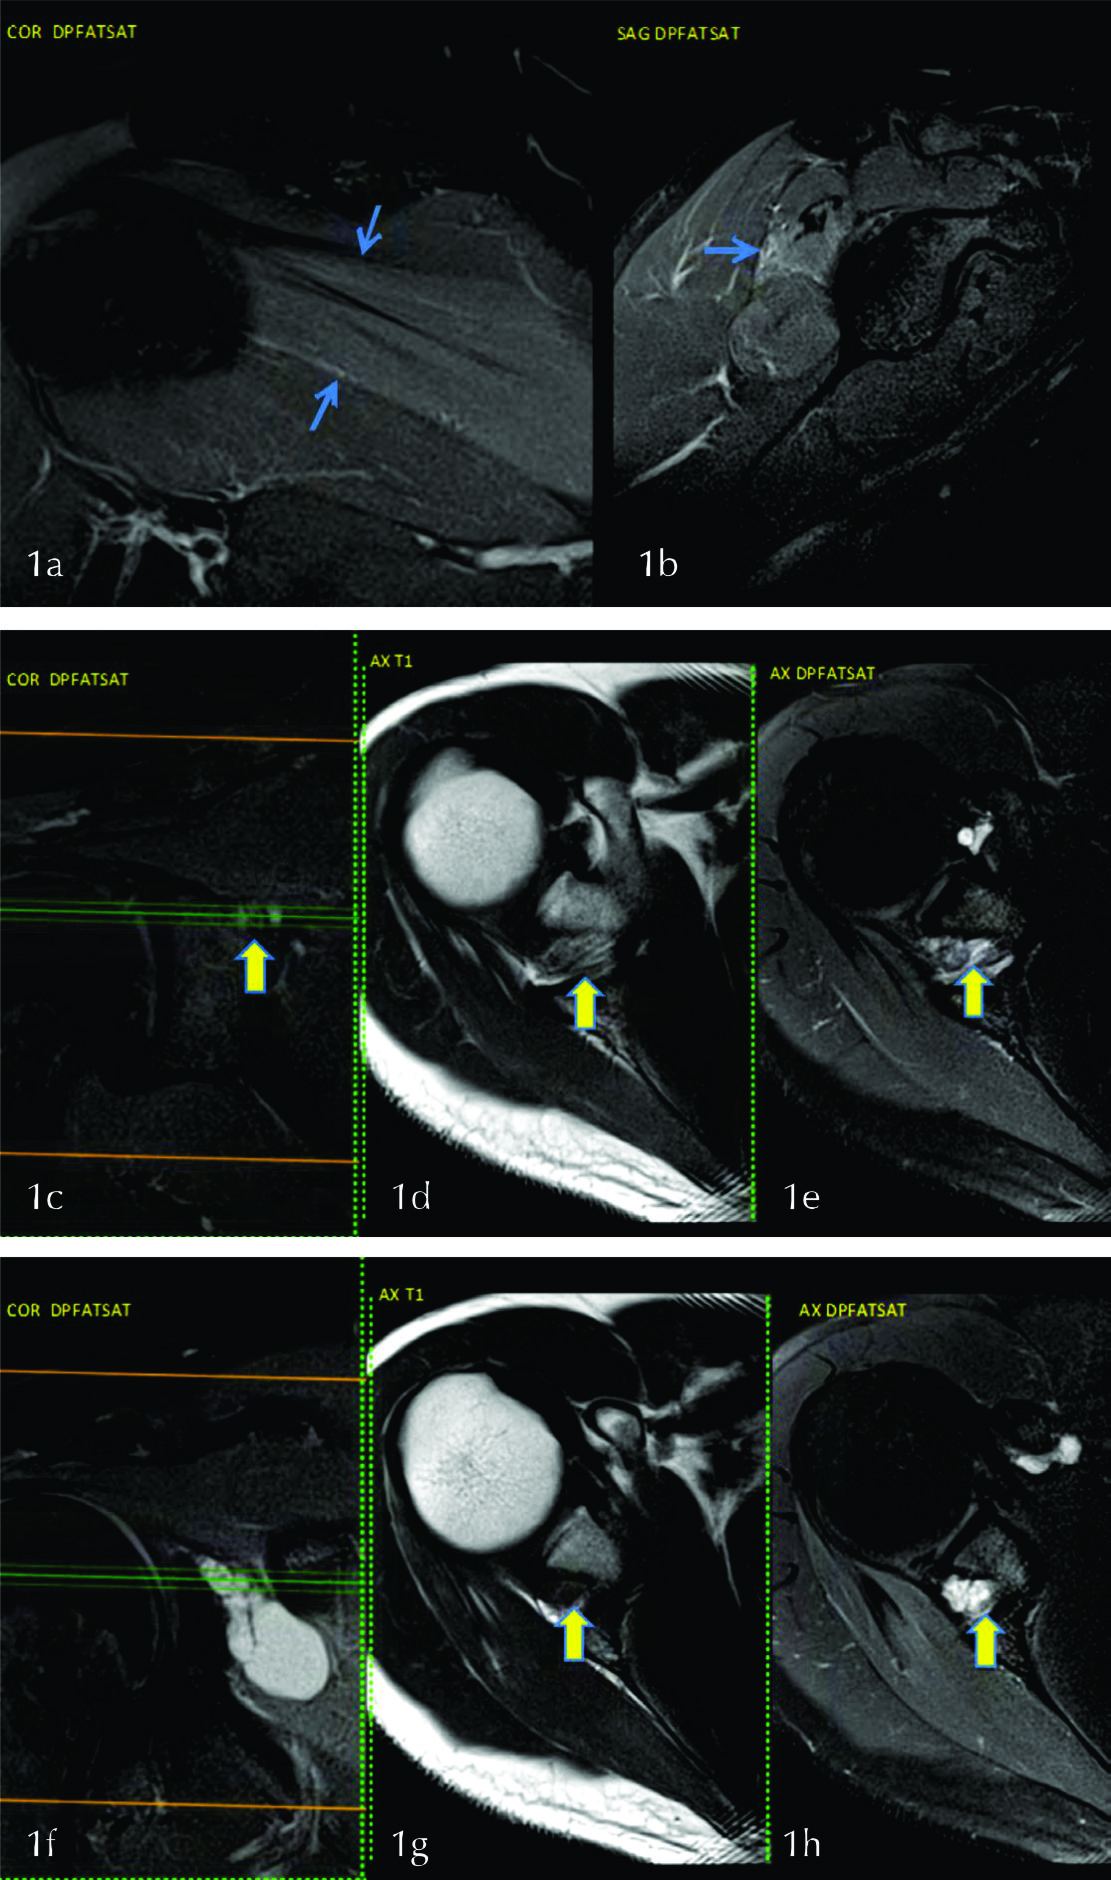

Figura 1

Se observa leve hiperseñal del musculo infraespinoso (flechas en a y b). Se identifica el nervio supraescapular en la escotadura espino glenoidea (flechas) en los planos coronal (c) y axial (d y e), las líneas en c indican la altura del corte en d y e. Quiste sinovial ocupando la escotadura espino-glenoidea en los planos coronal (f) y axial (flechas en g y h).

Figura 4

En las imágenes DP FAT SAT en los planos axial y sagital (a y b) se evidencia edema en los músculos deltoides y redondo menor (flechas celestes). En las secuencias T1 coronal y axial (c y d) se visualizan signos de atrofia de los mismos músculos (flechas verdes). Imágenes axial y coronal T1 (e y f) y axial DPfatsat (g) delimitando el espacio cuadrilátero donde se encuentra el nervio axilar (flecha).

Figura 7

a) imagen coronal en secuencia DPFATSAT donde se evidencia edema en la cabeza del peroné y gemelos en relación a contusiones. En la imagen axial b) se visualiza edema de la musculatura antero-externa de pierna. c,d,e) se observa el nervio peroneo en los planos axial y sagitales con engrosamiento y aumento de señal (flechas).